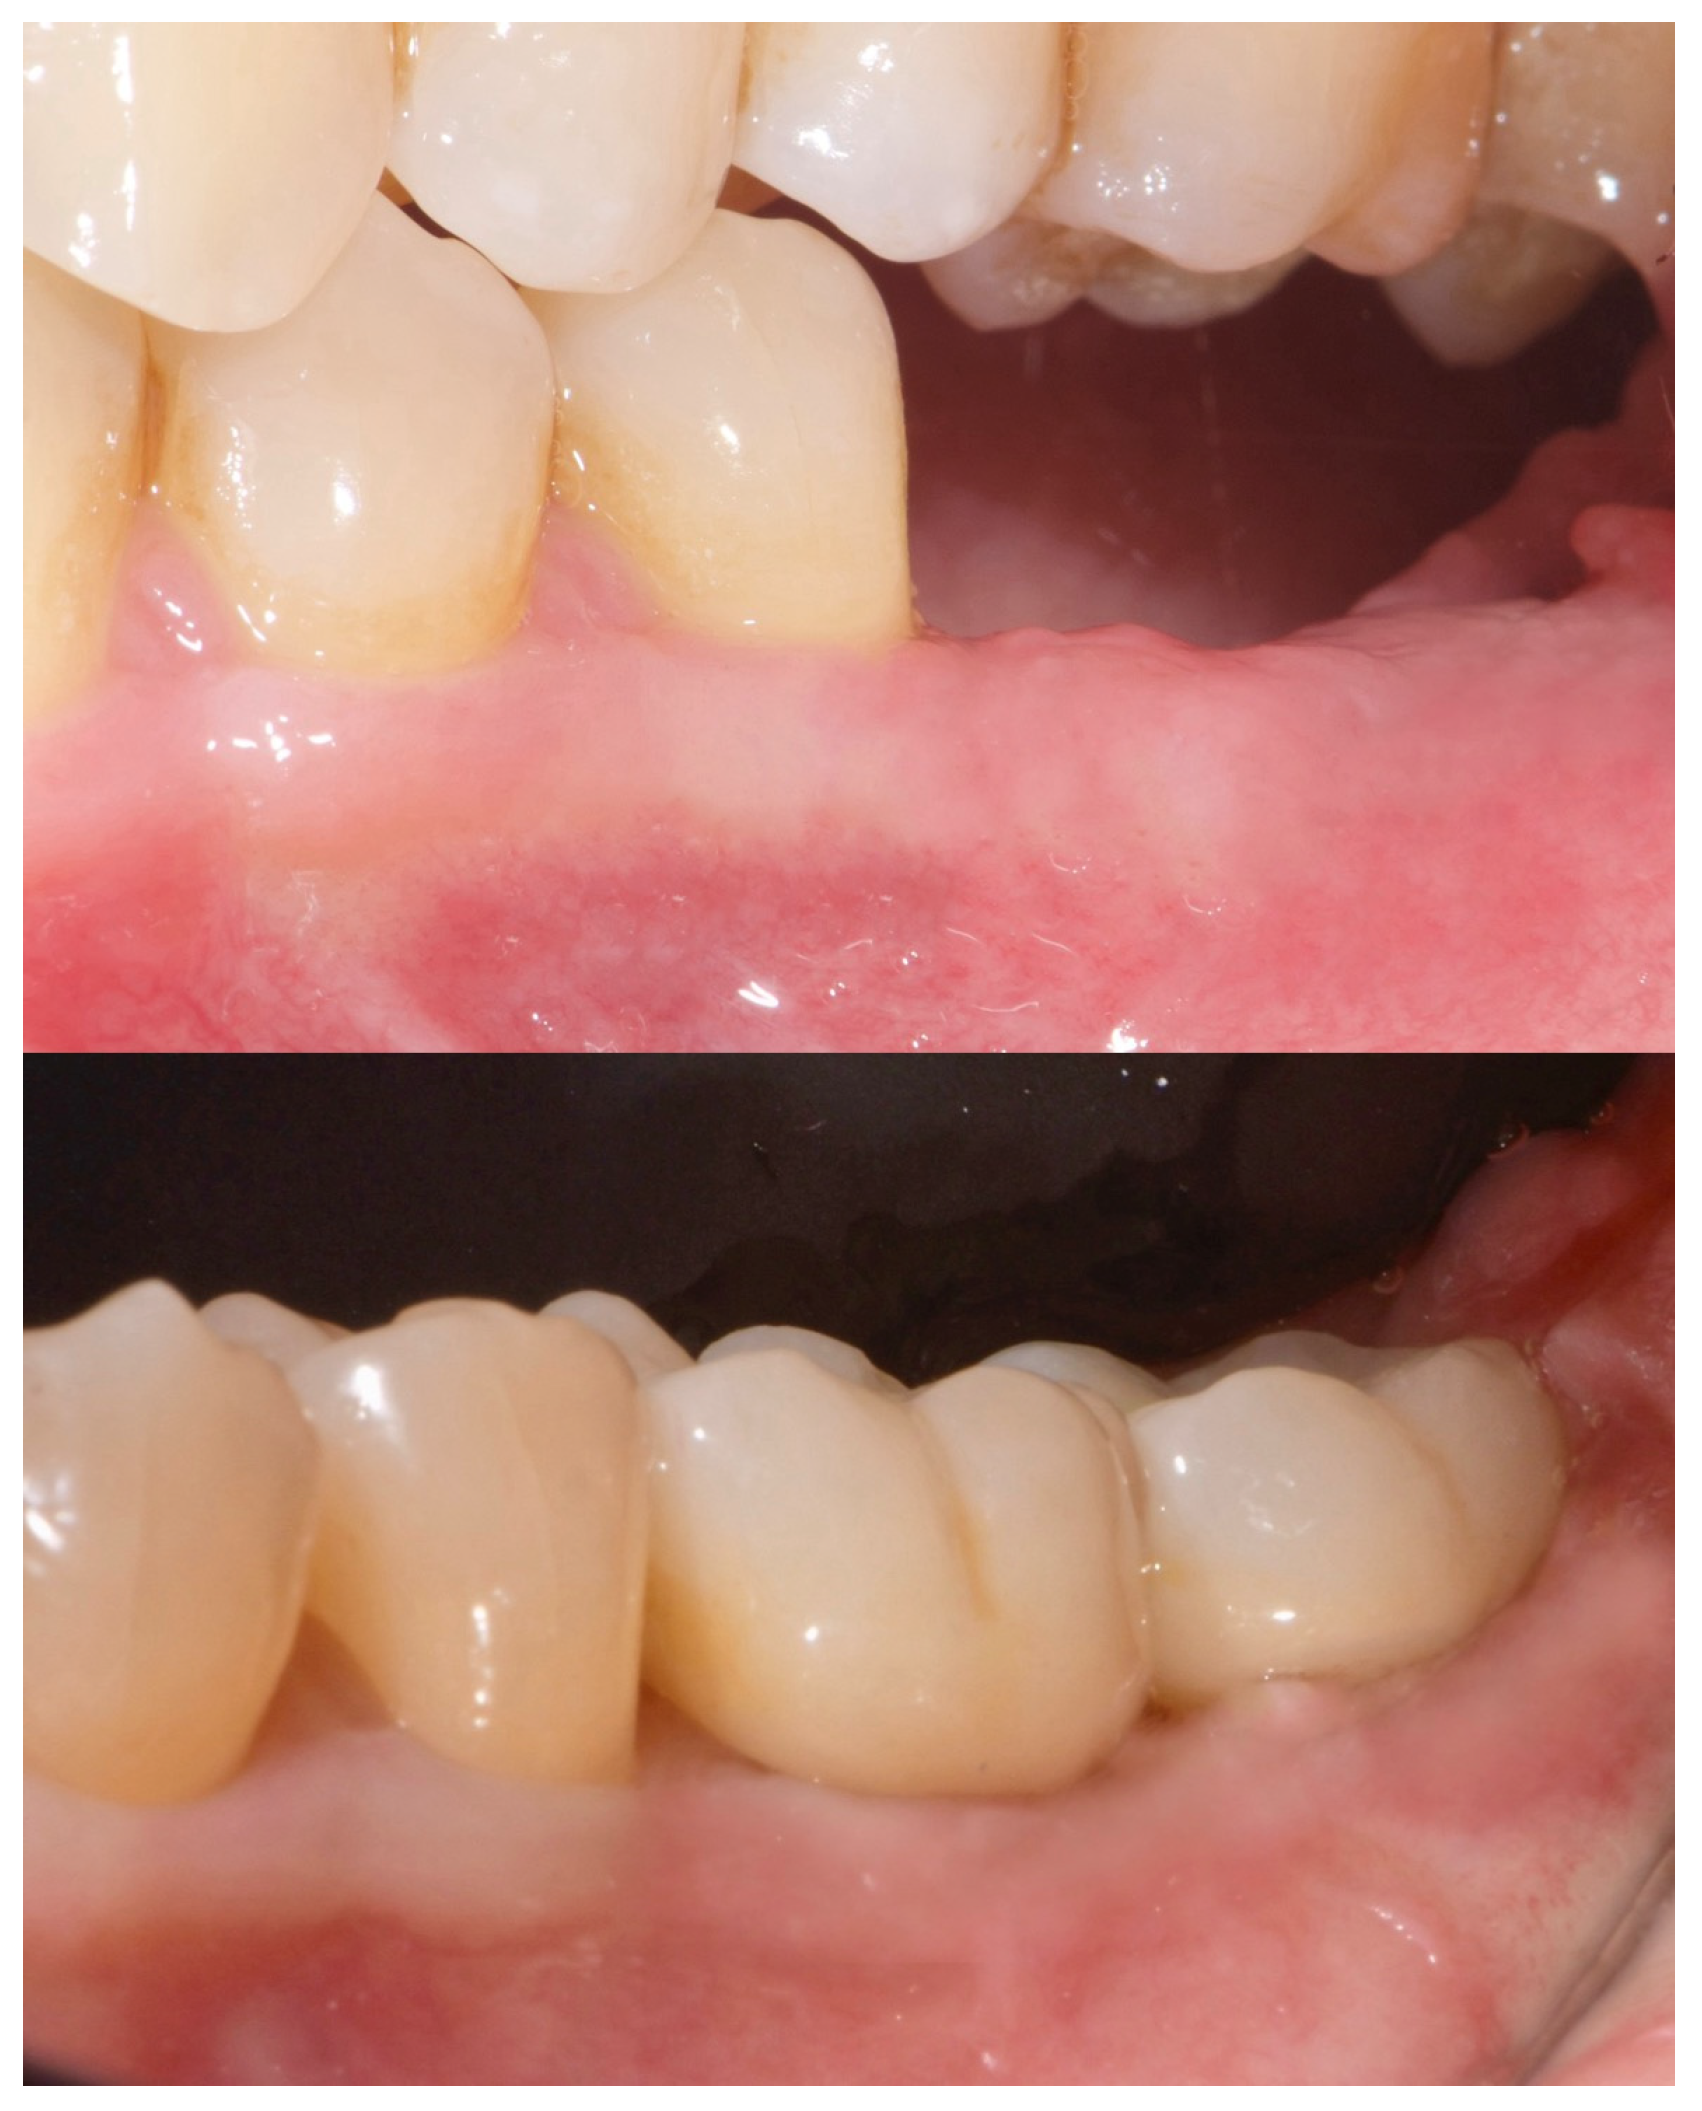

2. Case Summary